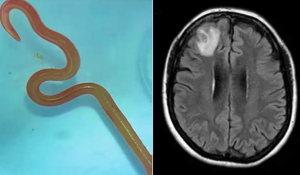

Depuis un an, les médecins cherchaient une infection : ils trouvent un ver de 8 cm dans son cerveau

https://fr.inf024.com/?p=442093

Elle consulte pour une simple toux, ce que les médecins trouvent dans son cerveau dépasse l’entendement

https://fr.inf024.com/?p=442194